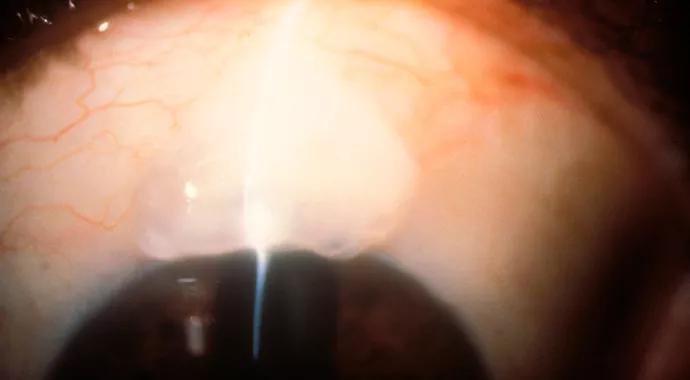

Each approach has its advantages and drawbacks. For example, ab interno trabeculotomy uses the Trabectome device. It relies on high frequency electrocautery to ablate the trabecular meshwork (TM) and inner wall of Schlemm’s canal (SC). Advantages include removal of the area of greatest resistance to aqueous outflow and tissue debris, which may reduce inflammatory stimuli, and as a result, potential post- surgical scarring. Complications include IOP spikes on the first day and intraoperative blood reflux from SC with subsequent hyphema.